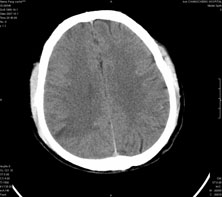

男,41岁,间断抽搐1小时,失神5分钟,bp130/90mmhg。低密度区ct值约16hu。

脑实质见多发散在的钙化点,右颞、顶叶见囊性灶,考虑脑囊虫。

脑实质见多发散在的钙化点,左顶叶见一囊变灶,多考虑脑囊虫。